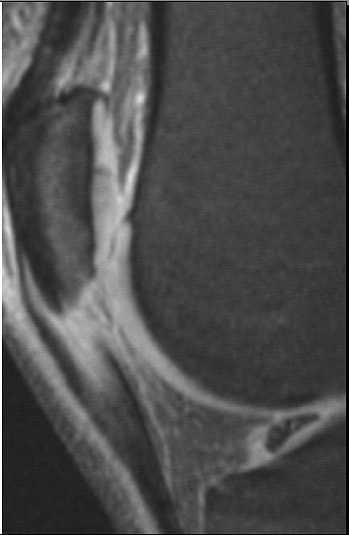

| Sagittal images of patellar tendinopathy or "jumper's knee" in a cyclist. Courtesy of Duke University Medical Center, Musculoskeletal Division, Durham, NC. |

How do cyclists get jumper's knee? "The repetitive flexion-extension process that goes around their knees can lead to strain on the patellar tendon," said Major, who sees many cycling athletes in her practice. "The tracking of that patella as it crosses the femur (causes) rubbing that can lead to problems in the joint space, and then with that tendon."